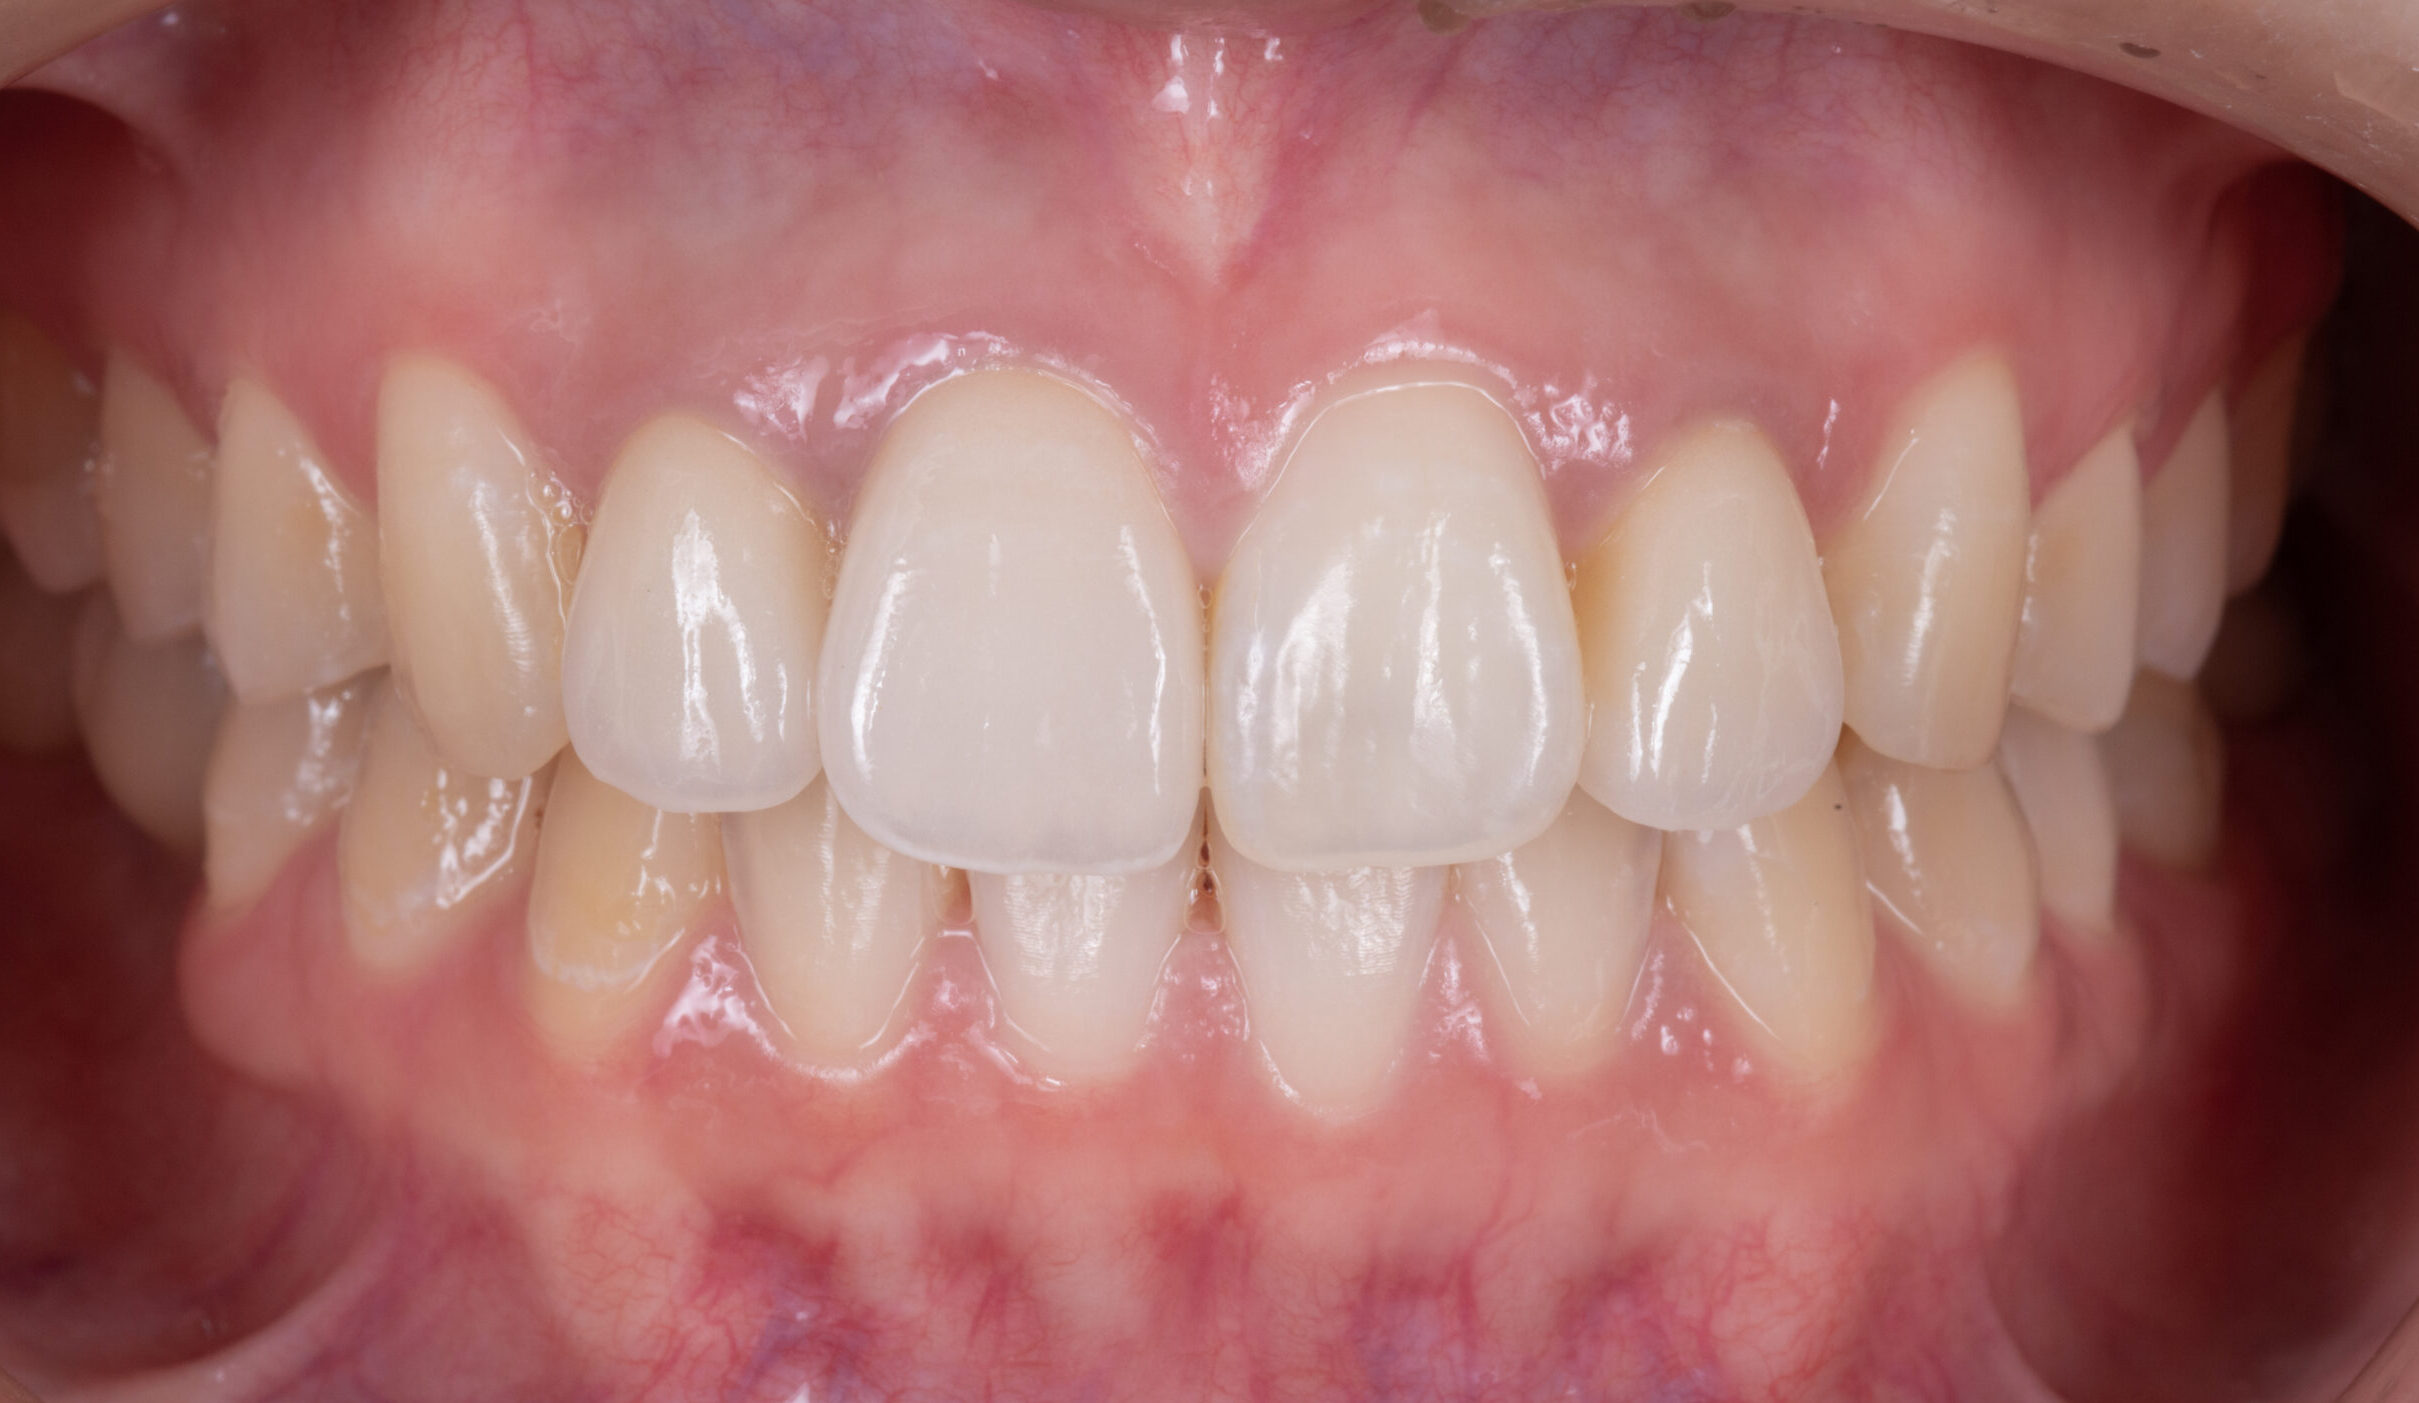

《最終》

今回の症例の治療概要としましては

①虫歯治療・根管治療

②マウスピース矯正(インビザライン)による歯列矯正

③インプラント埋入

④前歯部をセラミッククラウンへ

このような流れで治療させて頂きました。

写真の通り、とても綺麗な仕上がりに改善されました!

【最終】